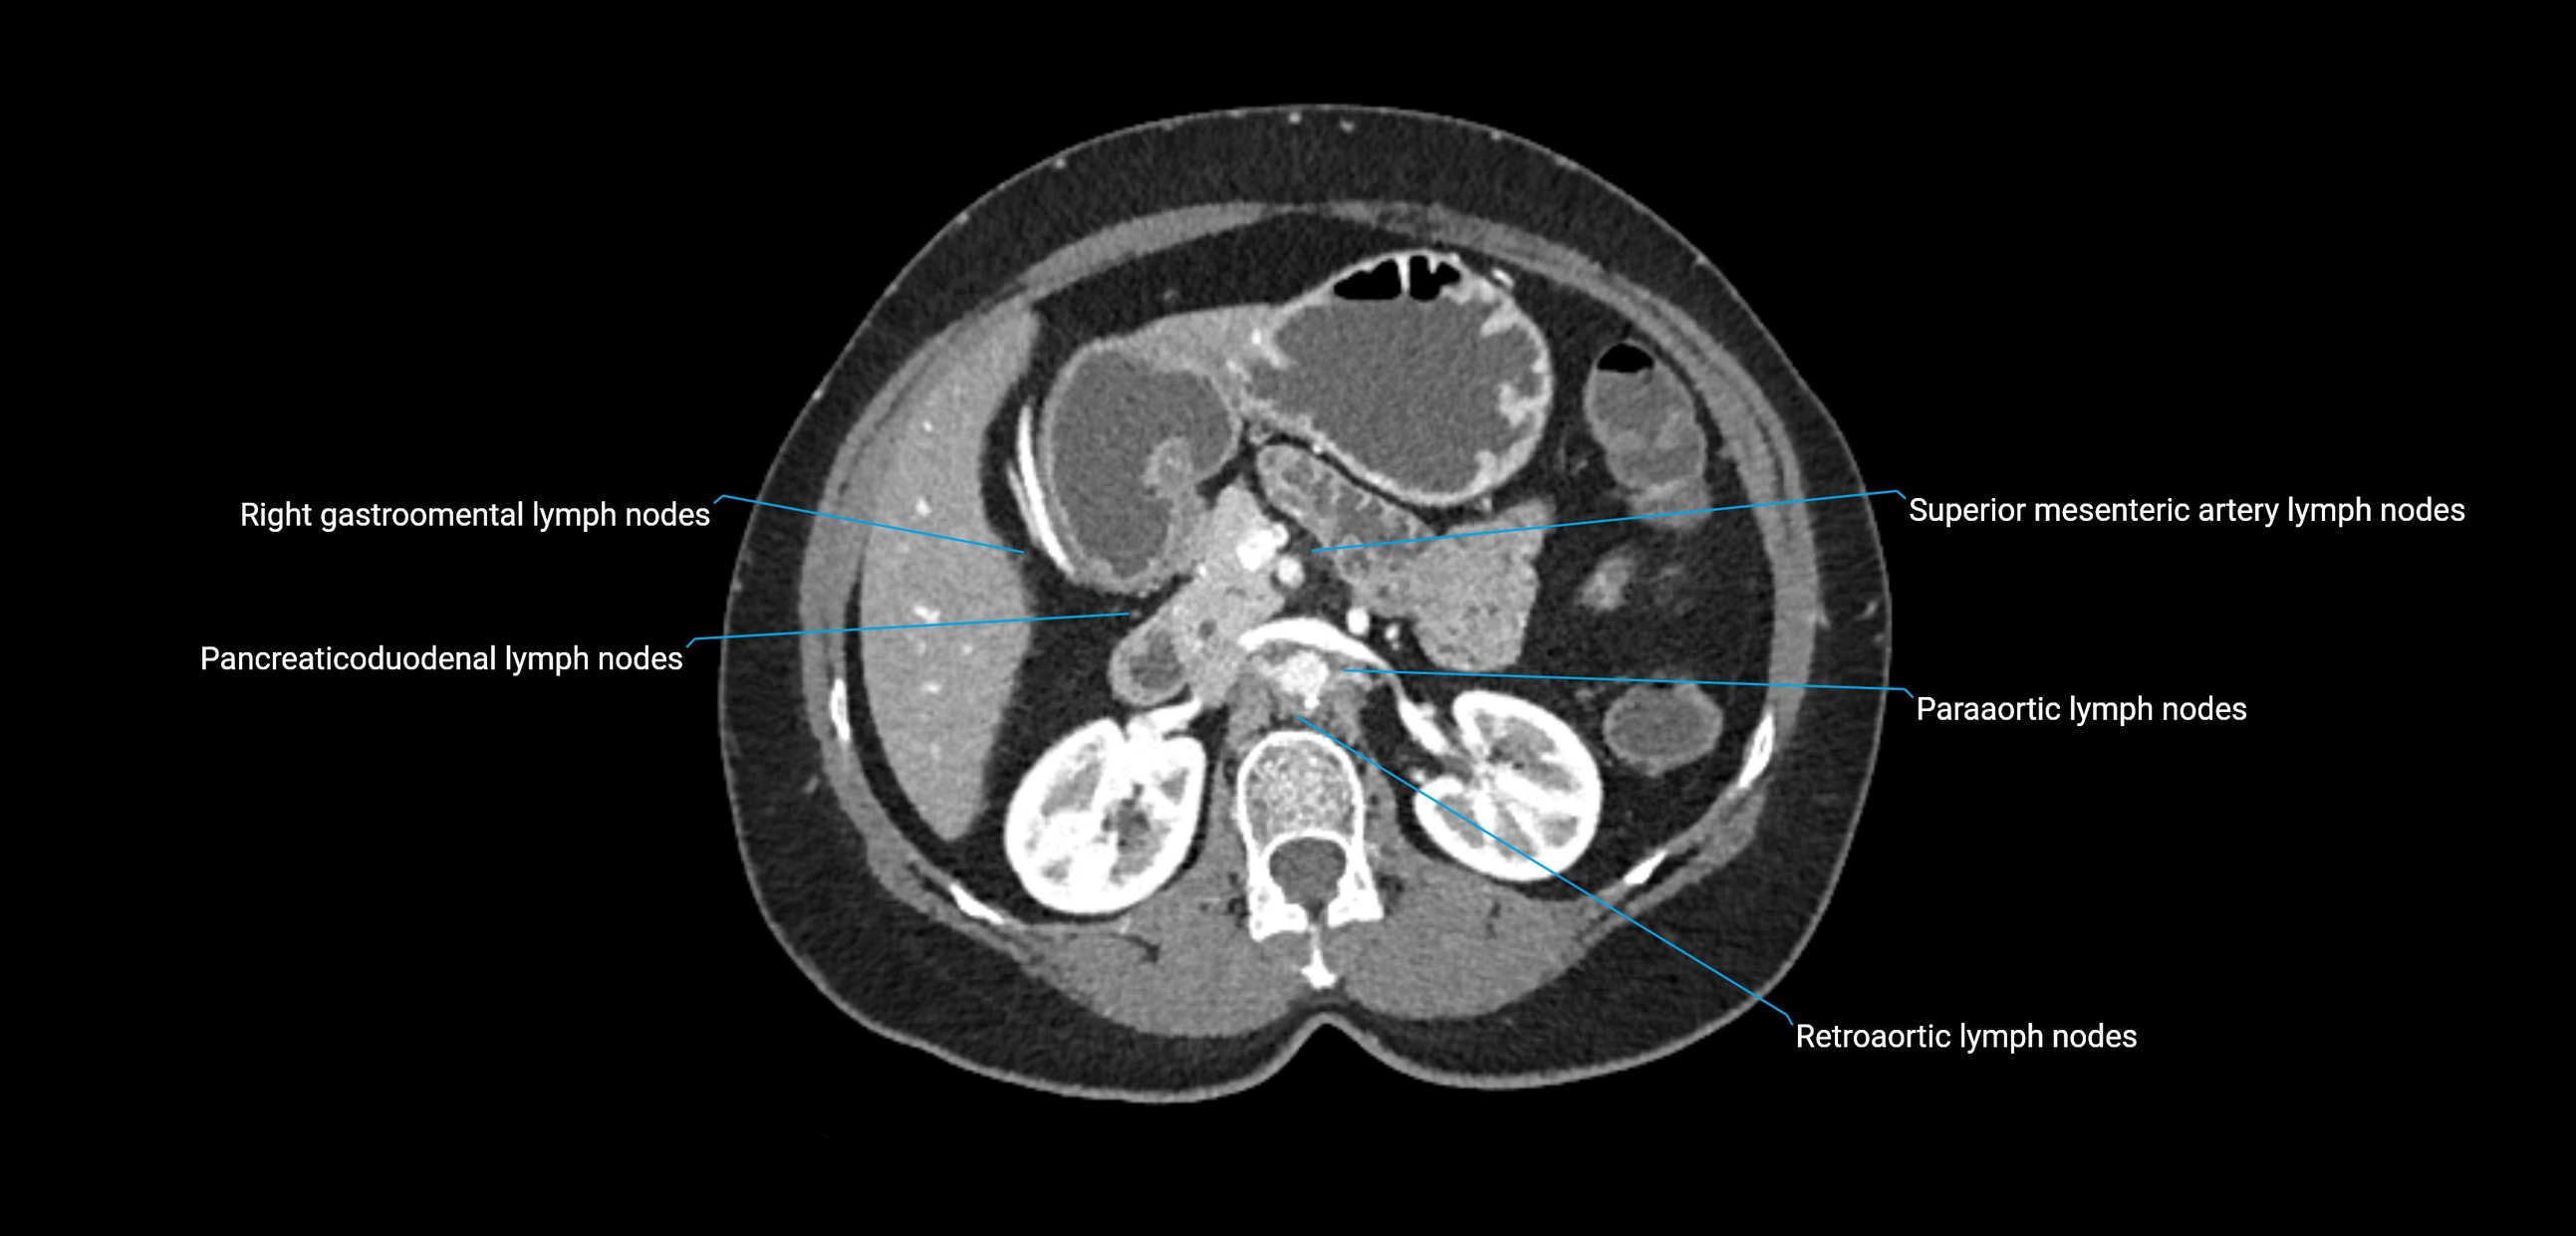

CT Appearance

CT Pre-Contrast:

• Nodes appear as soft-tissue density nodules adjacent to the aorta and IVC

• Calcification may be seen in chronic infections (e.g., tuberculosis)

CT Post-Contrast:

• Normal nodes enhance homogeneously

• Malignant nodes may show heterogeneous enhancement, central necrosis, or conglomerate formation

• Size >1 cm short axis is suspicious, though morphology and distribution are equally important